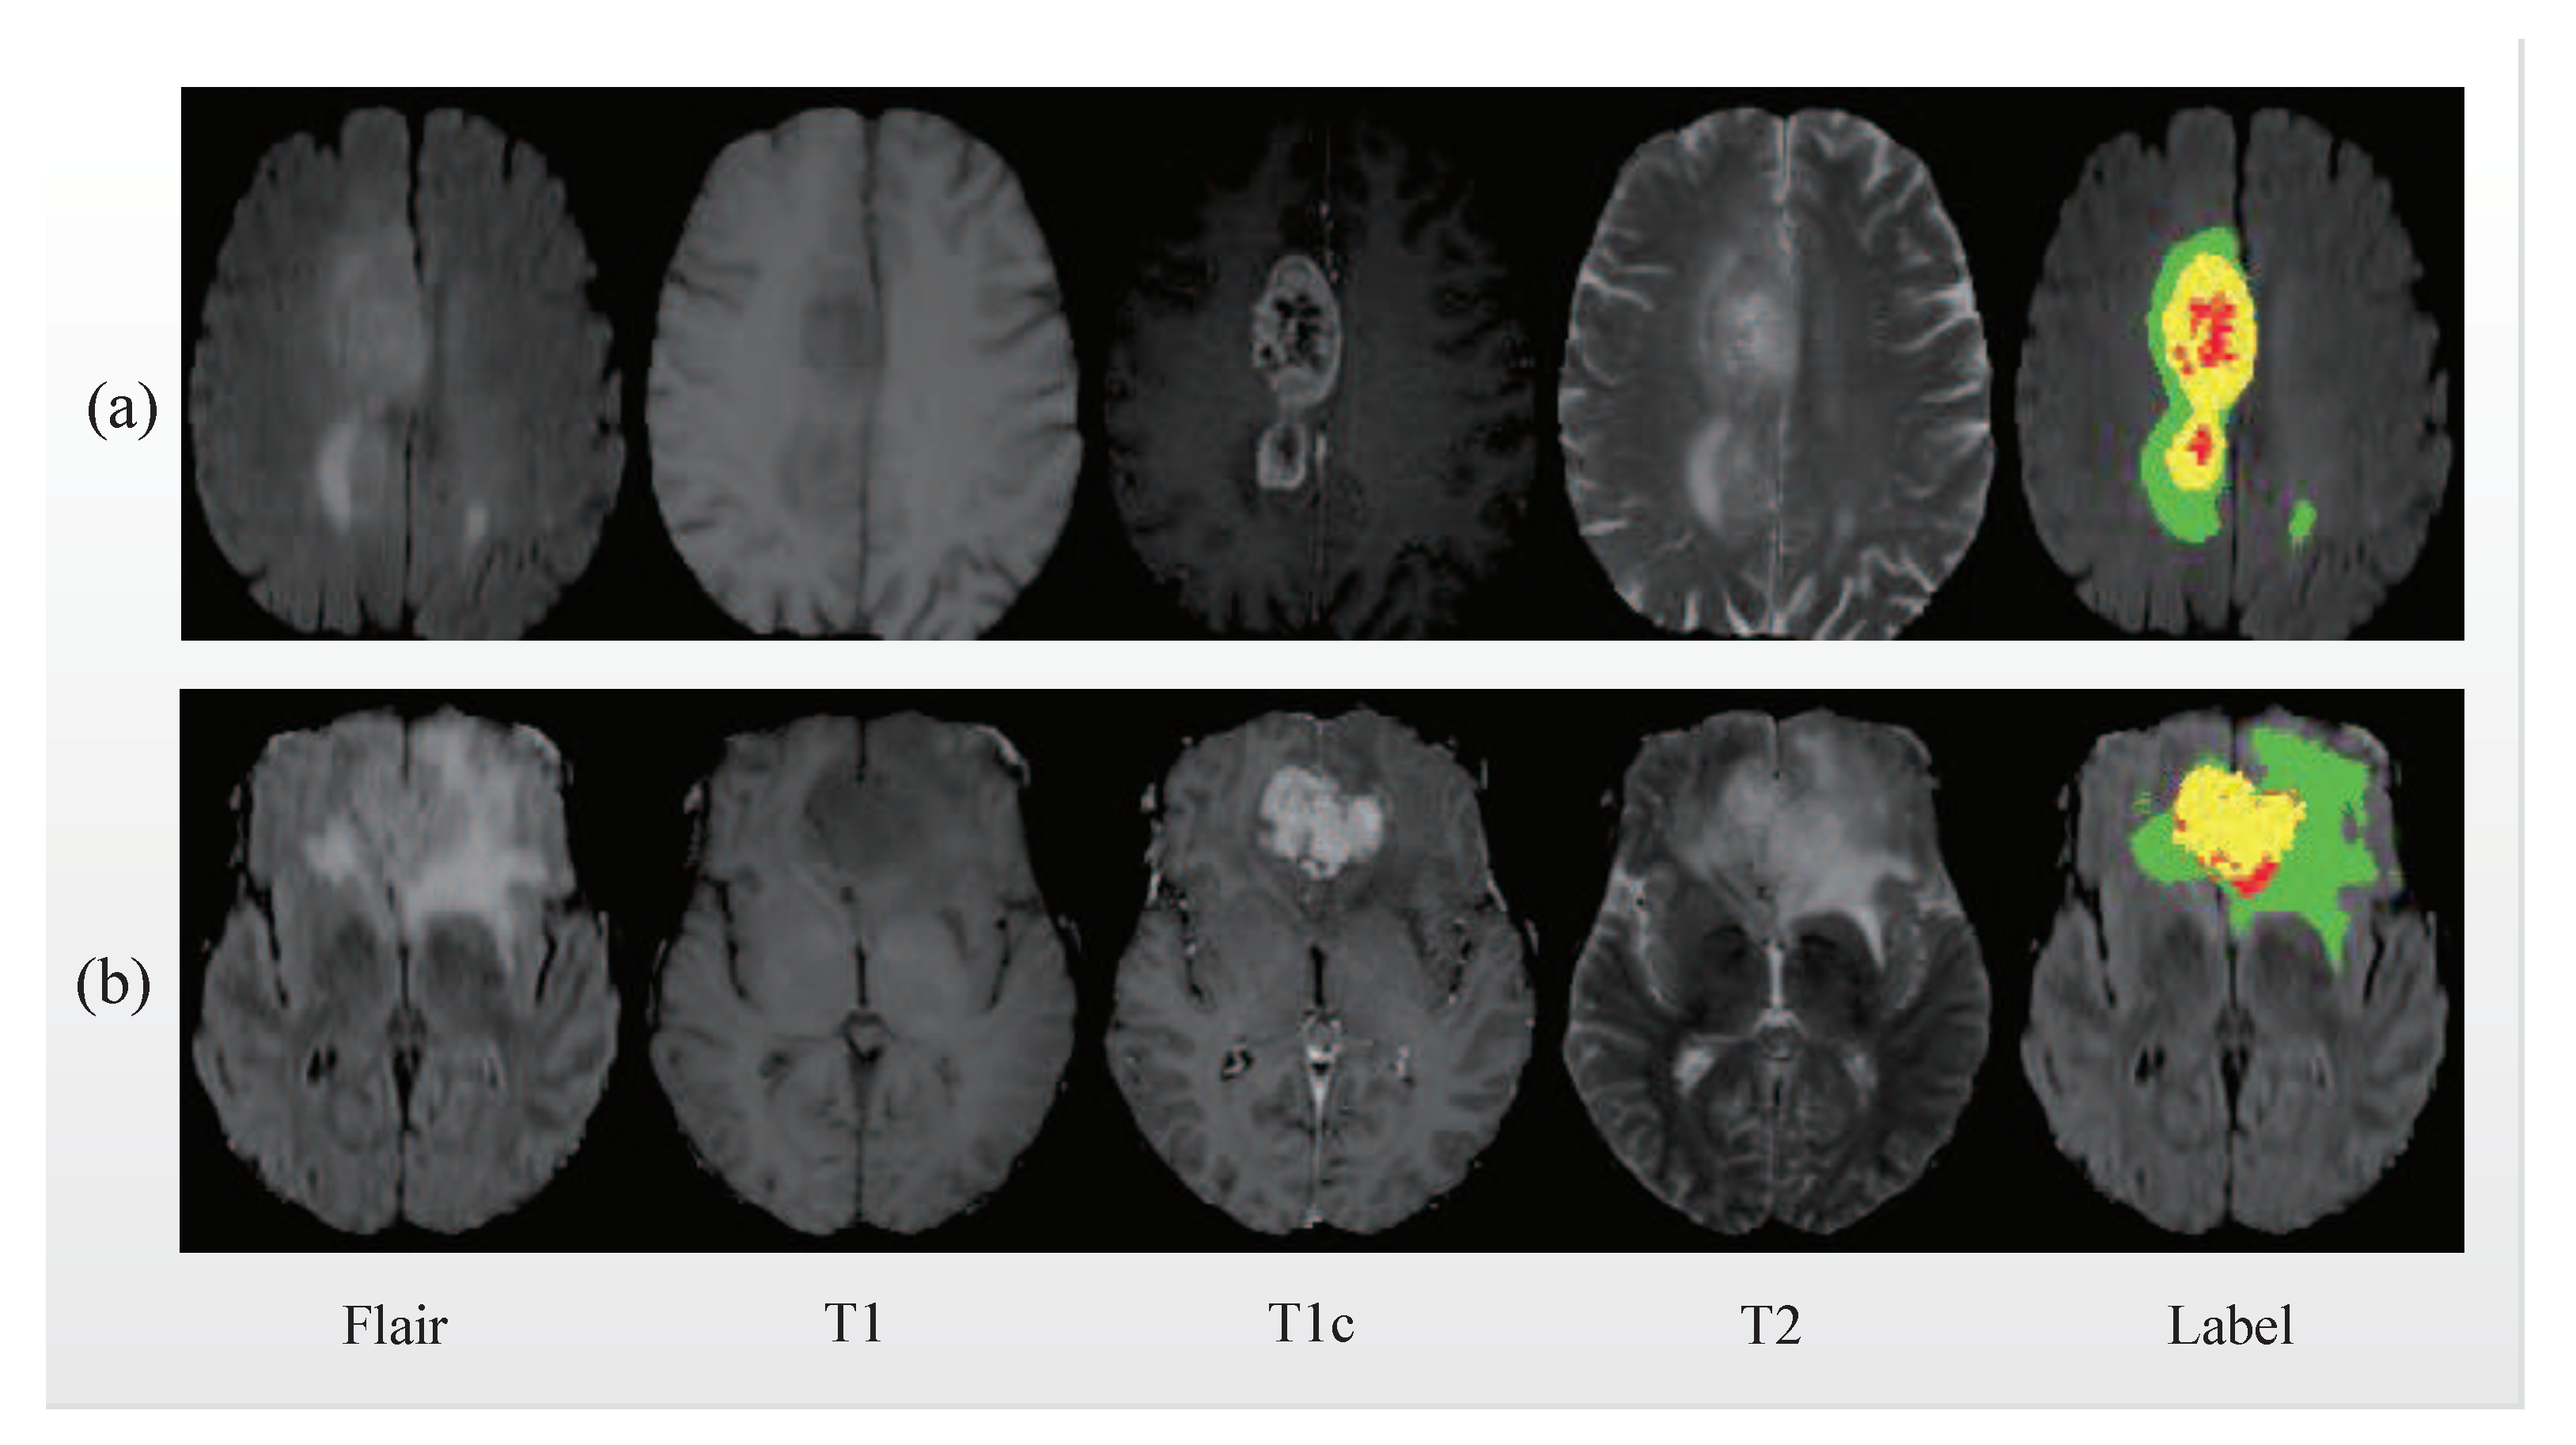

4.1. Datasets